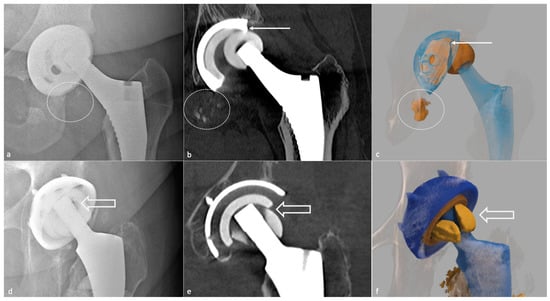

- Metallosis results from the shedding of metallic debris (secondary to a MoM prosthesis with corrosion, a conflict between a metallic acetabular cup and the prosthetic neck, or a contact between a metallic head and an acetabular metal back in case of PE wear or dislocation) that induces synovitis and an indolent pattern of osteolysis, potentially leading to loosening (i.e., potentially looking similar to osteolysis and PE wear). Synovitis may contain low-signal intensity or metallic density debris, causing MRI artifacts and bone erosion, best depicted on CT-MAR (Figure 20). Such debris might also be located in periprosthetic soft tissue and lymph nodes [54,57]. Metallic debris presence might also accentuate PE wear (i.e., third fragment wear) [54]. Of note, high serum metal-ion levels can be found in symptomatic and asymptomatic patients and would be associated with pseudo-tumors, so that such a biological finding should lead to the prescription of an MRI to rule out a pseudo-tumor even in asymptomatic patients [6,103].